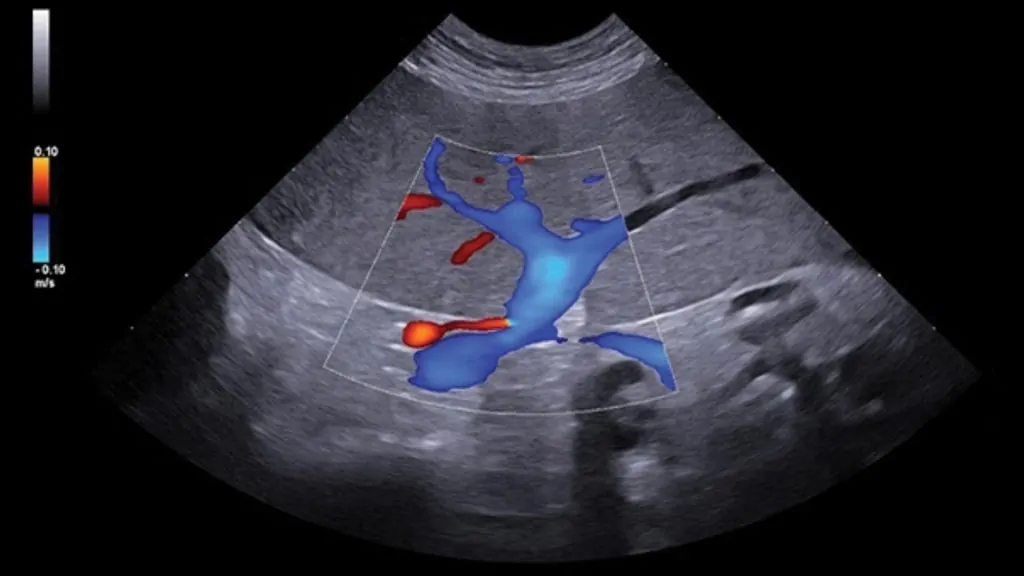

Karaciğer parankimi, portal/hepatik damarlar, safra kesesi ve biliyer sistem değerlendirilir.

Gerekli durumlarda Doppler ile vasküler yapıların analizi yapılabilir; portosistemik şant şüphesinde yönlendirici olabilir.